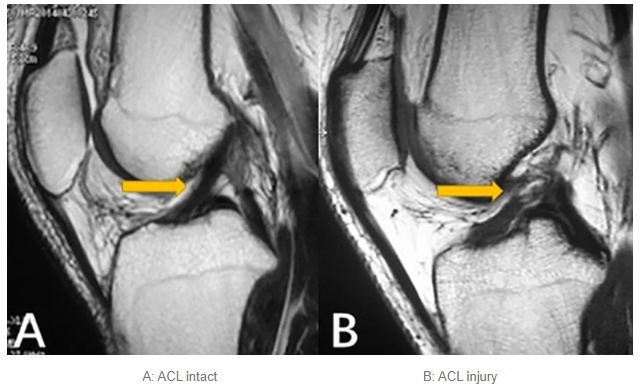

영상검사: MRI가 가장 정확하며 인대 손상 정도, 반월상 연골판, 기타 동반 손상 확인에 필수적.